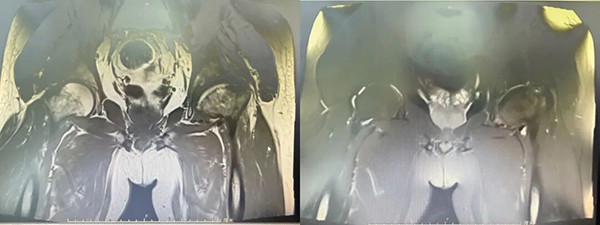

术前X线: